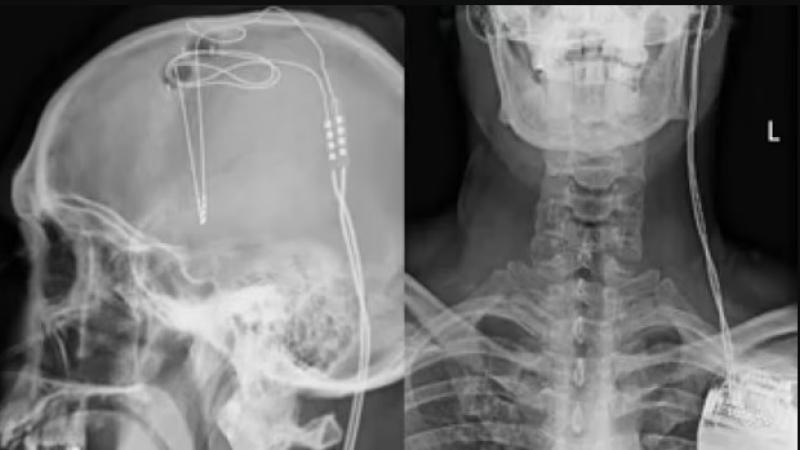

يتضمن العلاج الجديد على إدخال أقطاب كهربائية صغيرة في فتحتين صغيرتين محفورتين في الجمجمة، وإدخالهما في منطقة المكافأة في الدماغ.

وقال الباحثون، تقع المنطقة المستهدفة، التي تسمى (النواة المتكئة)، في منتصف الدماغ، وعندما تصل الموجات فوق الصوتية إلى هذه المنطقة، فإنها تتسبب في اهتزاز أغشية الخلايا وتعطيل نظام المكافأة الذي يعانيه الأشخاص مما يؤدي إلى الإدمان.